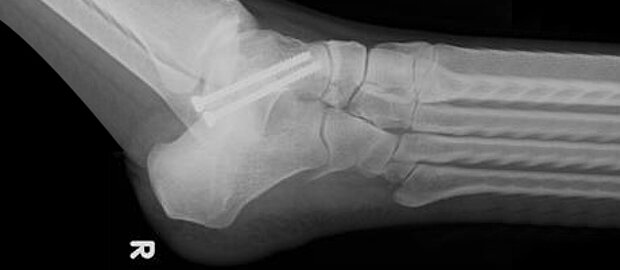

- Calcaneusfraktur (Bruch des Fersenbeines)

Zum Einsatz kommen moderne operative Behandlungsmethoden und Osteosyntheseverfahren. Implantiert werden Stahl- und Titanmaterialien: Schrauben, Platten, winkelstabile Platten, kanülierte Schrauben, Kirschner-Drähte, Kleinfragmentplatten und externe Fixateure.